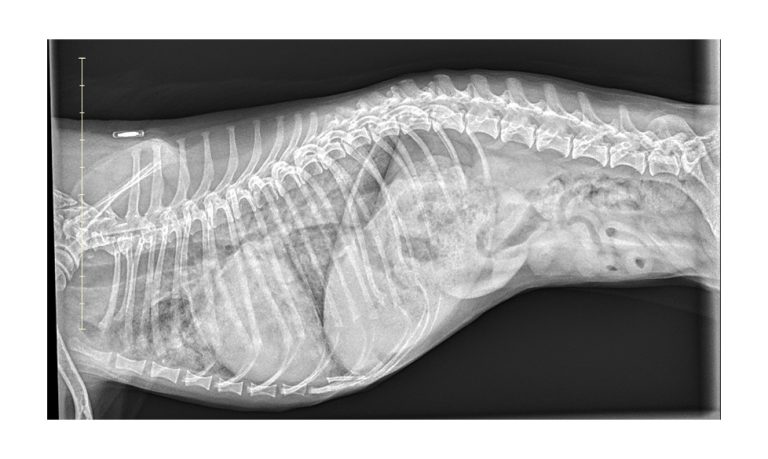

Small Animal Digital X-Ray

State of the art digital radiography systems that will move your clinic into the modern world of digital x-ray paired with our easy to use cloud archiving & viewing software.

No more waiting for x-rays, acquisition time is 3 seconds from the moment you hit the exposure button. This is a great improvement to the overall workflow which will cut x-ray time to less than half when compared with traditional systems.

At VUE IT, we have over 10 years of experience in medical imaging, our expertise in digital radiology is second to none. Our clients benefit from access to a wide range of X-ray systems, as well as support for existing systems, including top-ranked Canon DR and Fuji DR/CR systems.